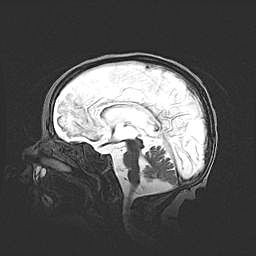

Неполная лизэнцефалия (пахигирия). Открытая гидроцефалия.

Возраст: 17 дней

Вес: 3110 г

Пол: мужской

Окружность головы: 33,5 см

Срок гестации: 35-36 недель

Лизэнцефалия—недоразвитие корковой пластинки и мозговых извилин в результате нарушения миграции нейронов коры. Поверхность мозговых полушарий гладкая. Микроскопически выявляется отсутствие нормальных слоев коры и скопление групп нейронов в подкорковом белом веществе.

Пахигирия—уменьшение числа вторичных извилин. В пораженном полушарии нервные клетки образуют толстый недифференцированный слой с неправильно расположенными нервными волокнами и группами гетеротопных клеток. Нервные клетки незрелые. Белое вещество истончено. При этом нередко аномально развит корково-спинномозговой путь.